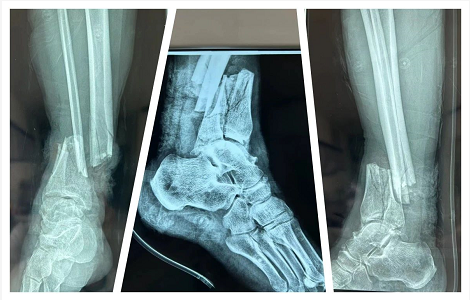

2022年8月,突如其来的“伤害”让曹先生深受重创。“当时我合计的是脚肯定保不住了,我是抱着一定得截肢的想法来医院的。”让曹先生没想到的是,手足显微外科主任田宽亮主任用“Ilizarov环形外架技术”保住了濒临截肢的脚。